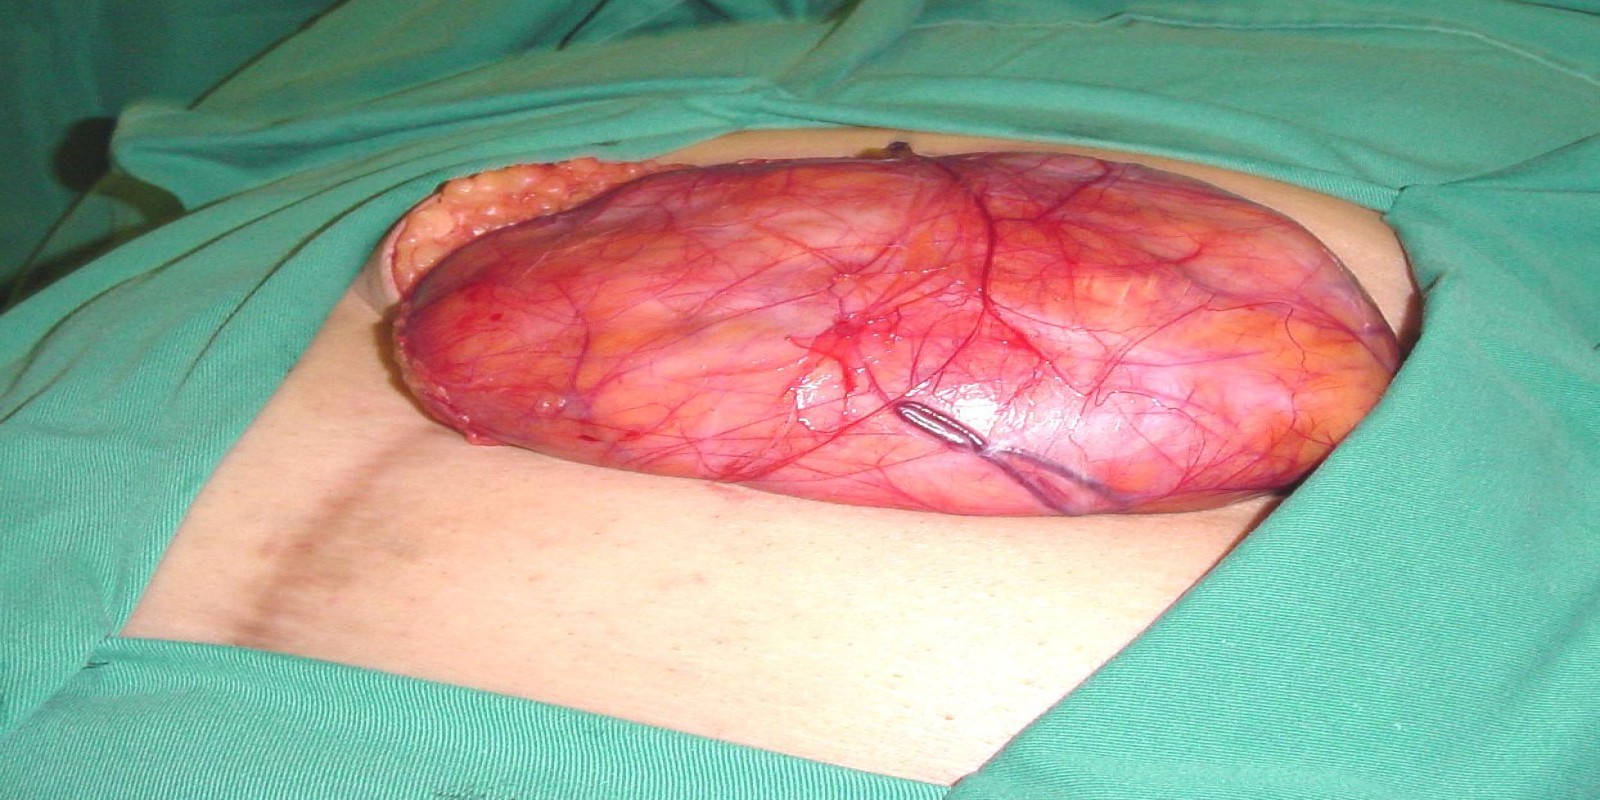

Caso Código 127A de Hérnia Incisional

Cod.: 127A